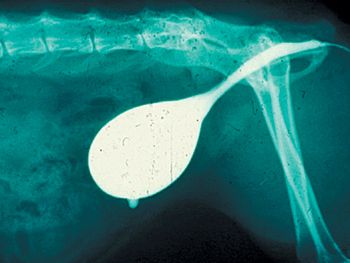

Correct answer for Image Quiz: Cytology-A subcutaneous mass in a senior dog